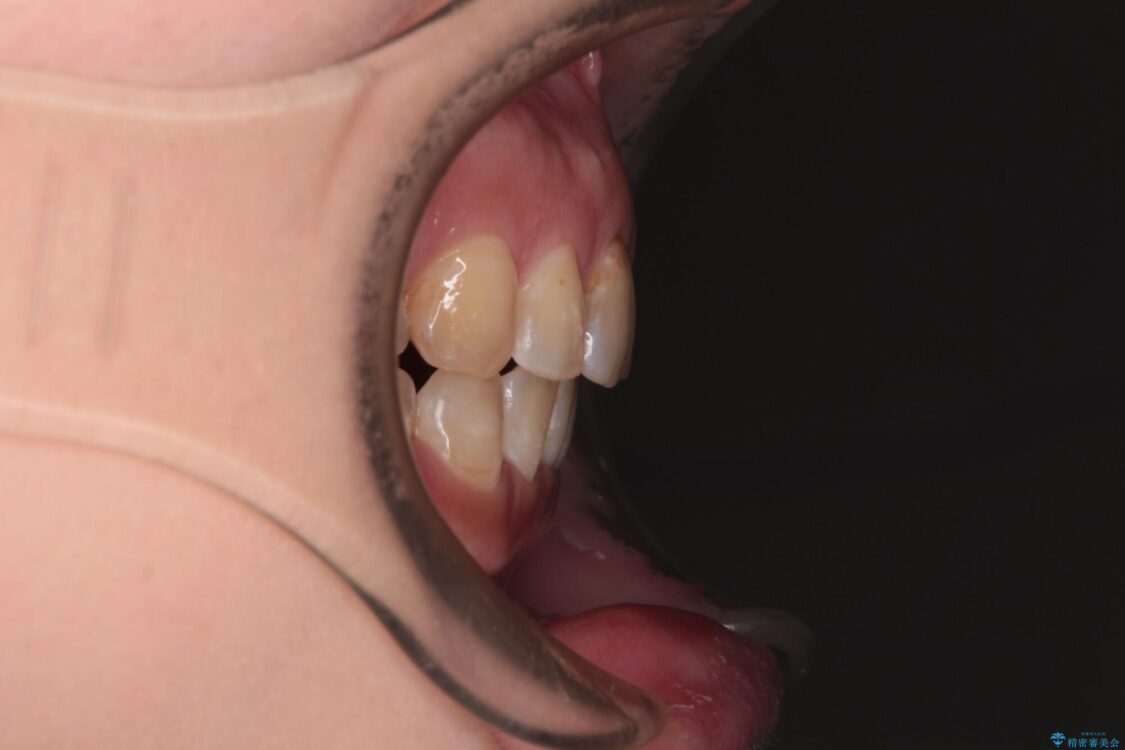

飛び出た上の前歯を気にして来院された患者様です。

奥歯の咬み合わせは、上顎歯列が理想的な一よりも数mm前方にある状態でした。

治療前

• 【モニター】飛び出た前歯を整えたい ワイヤー矯正治療 治療前画像